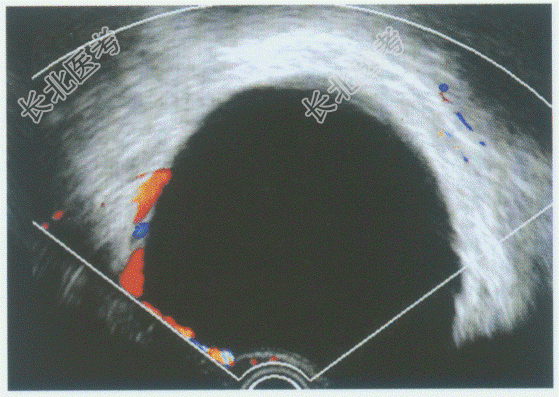

- 单项选择题临床资料:女性患者, 57岁,自述下腹部进行性增大不适半年余。妇科内诊: 左附件区触及拳头大肿物。

超声综合描述:经阴道扫查左附件区可见8.0cm×6.1cm无回声区, 边界清晰,形态规则, 内见少许分隔,CDFI: 无回声周边可见条样血流信号。见下图及彩图。